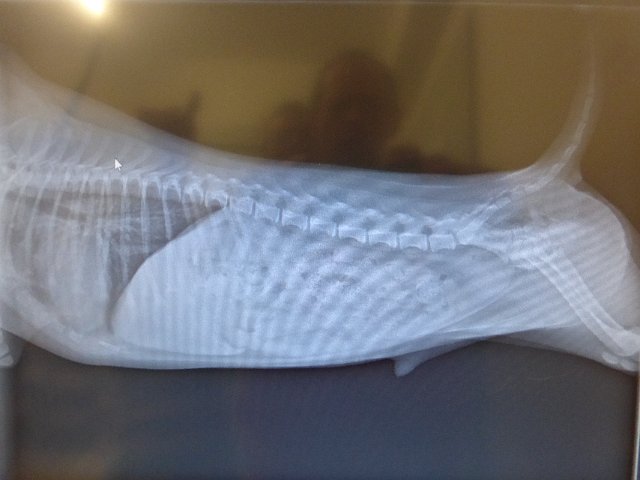

P1240551